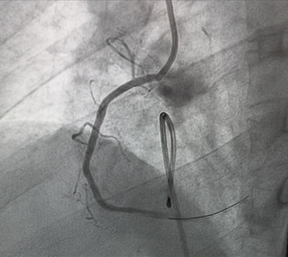

The patient was transferred to the catheterization laboratory for emergent coronary angiography. This revealed a complete thrombotic occlusion of the first segment of the right coronary artery (RCA) (Figure 3). A percutaneous coronary intervention (PCI) was performed, with successful placement of a drug-eluting stent (DES), achieving TIMI grade 3 flow. (Figure 4).

Figure 4: Percutaneous coronary intervention of CDI with

successful result